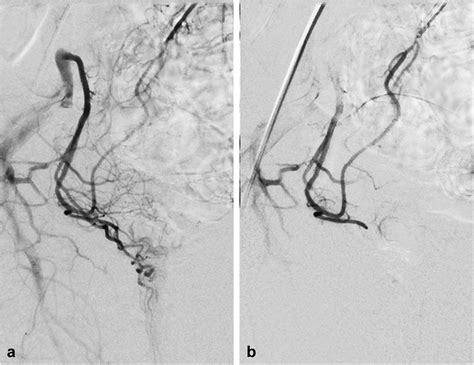

Because it is a minimally invasive technique, it does not require general anesthesia or incisions in the sensitive anal region. Instead, a tiny catheter is guided through a blood vessel in the wrist or groin to the specific arteries supplying the hemorrhoids. Small particles are then injected to block these vessels, successfully reducing the pressure and engorgement of the hemorrhoidal tissues.

2. Guidance: Using real-time X-ray imaging (fluoroscopy), the radiologist navigates a microcatheter through the vascular system.

3. Embolization: Once the specific hemorrhoidal arteries are identified, specialized embolic agents are injected to reduce the blood supply.